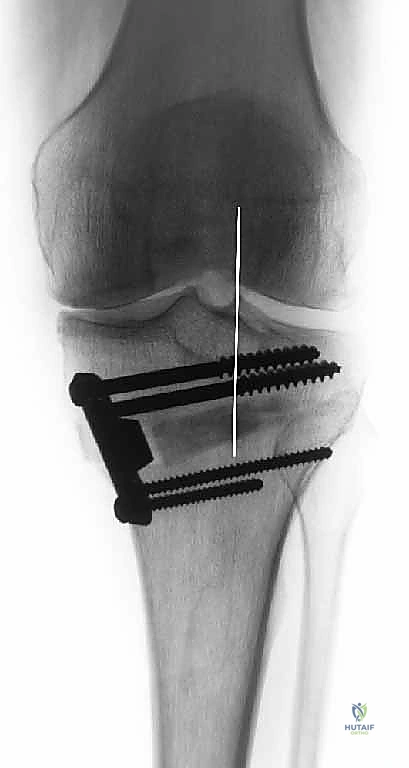

قبل العملية، يتم قياس زوايا الركبة بدقة متناهية. كل درجة من درجات التعديل يتم حسابها مسبقاً.

استخدام التخطيط الرقمي يضمن عدم حدوث تصحيح مفرط (Over-correction) أو تصحيح ناقص (Under-correction)، وهو ما يميز الجراح الخبير عن غيره.

3. إجراء القطع العظمي (The Osteotomy):

باستخدام أدوات دقيقة ومناشير جراحية متطورة، يتم عمل قطع غير مكتمل في عظمة الساق. هناك طريقتان رئيسيتان:

* الشق المفتوح (Opening Wedge): يتم فتح العظم من الداخل وإضافة طعم عظمي (صناعي أو طبيعي) لملء الفراغ وتعديل الزاوية. وهي الطريقة الأكثر شيوعاً حالياً.

* الشق المغلق (Closing Wedge): يتم إزالة إسفين (مثلث) صغير من العظم من الجهة الخارجية وإغلاق الفراغ.

4. تعديل المحور:

يتم فتح العظم تدريجياً وببطء شديد حتى الوصول إلى الزاوية التي تم حسابها في التخطيط الرقمي قبل الجراحة.